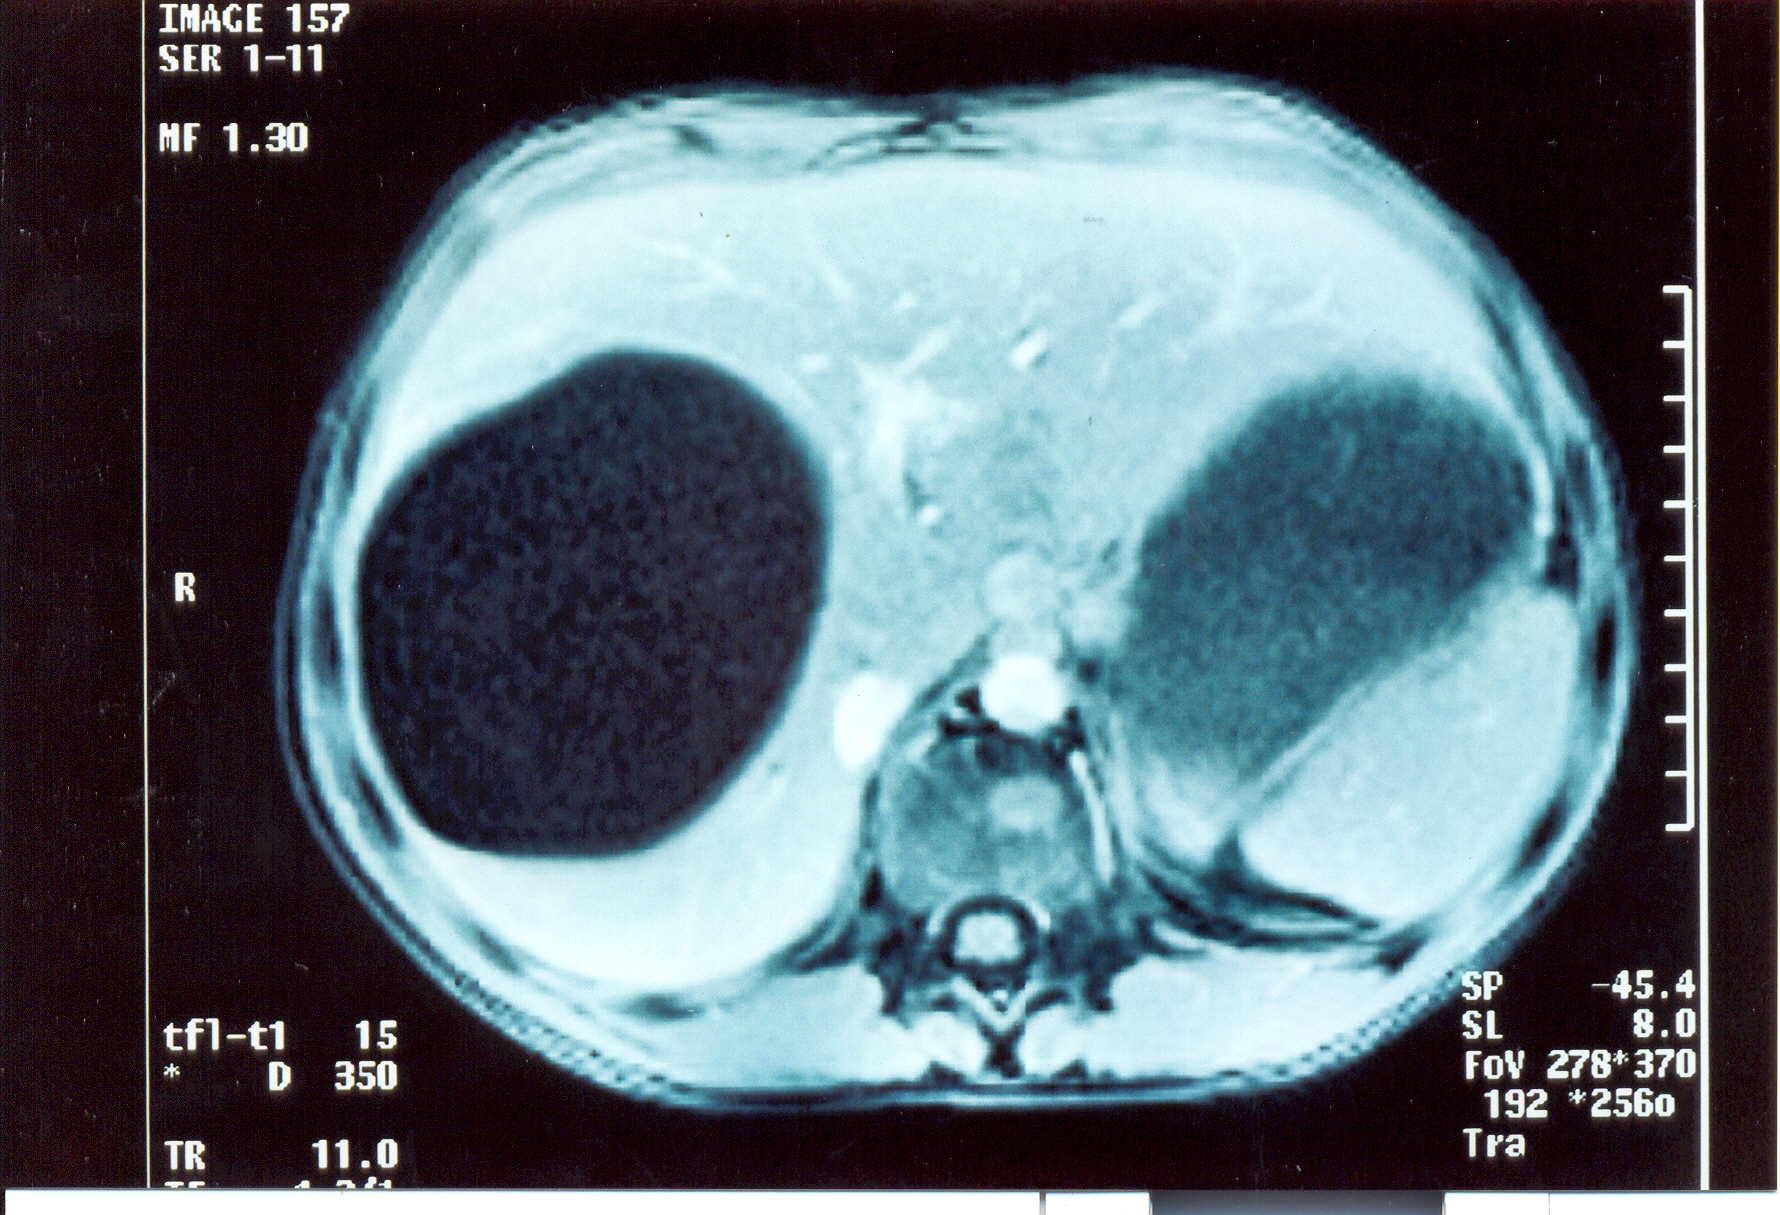

Abdominal computed tomography. Cystic lesion of the right lung. Courtesy Dr. V. Penopoulos.